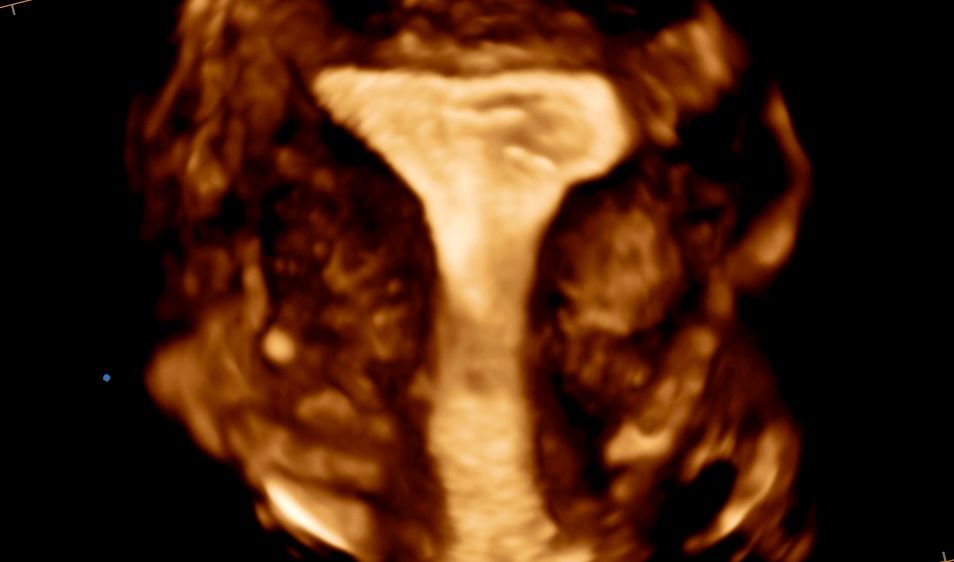

Sono Walter Alio, specialista in Ginecologia e Ostetricia. Da Luglio 2013 sono Dirigente Medico di I livello presso l'ARNAS Civico di Palermo. Mi occupo di gravidanza,diagnosi prenatale e della diagnosi e cura delle patologie ginecologiche. In particolare ho focalizzato la mia attenzione negli anni sulla diagnosi e cura dell'Endometriosi e sulla pratica dell'endoscopia ginecologica (laparoscopia e isteroscopia). Mi avvalgo delle consulenze della Dr.ssa Valentina Giampaolo, psicologo e psicoterapeuta per terapia individuale e di coppia per problematiche della sfera sessuale e della Dr.ssa Laura Napoli nutrizionista.

• Ecografia

• Ecografia ginecologica

• Ecografia morfologica